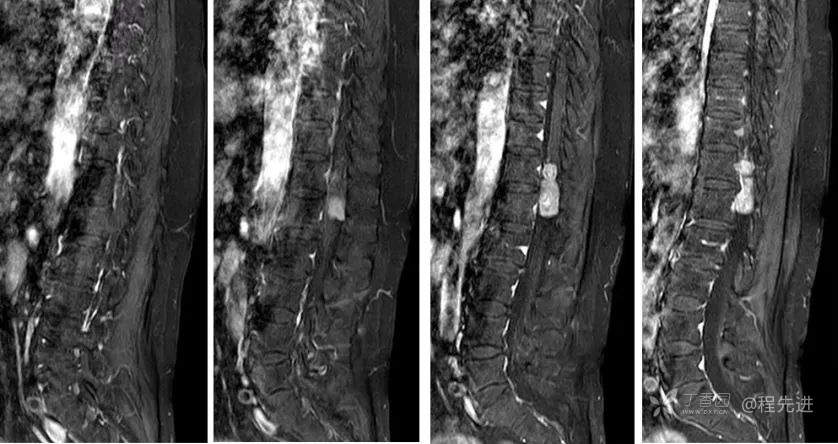

MR: